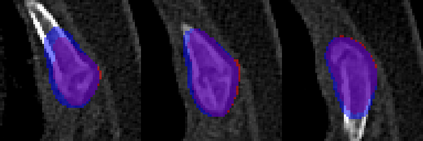

Rib fractures are a common and potentially severe injury that can be challenging and labor-intensive to detect in CT scans. While there have been efforts to address this field, the lack of large-scale annotated datasets and evaluation benchmarks has hindered the development and validation of deep learning algorithms. To address this issue, the RibFrac Challenge was introduced, providing a benchmark dataset of over 5,000 rib fractures from 660 CT scans, with voxel-level instance mask annotations and diagnosis labels for four clinical categories (buckle, nondisplaced, displaced, or segmental). The challenge includes two tracks: a detection (instance segmentation) track evaluated by an FROC-style metric and a classification track evaluated by an F1-style metric. During the MICCAI 2020 challenge period, 243 results were evaluated, and seven teams were invited to participate in the challenge summary. The analysis revealed that several top rib fracture detection solutions achieved performance comparable or even better than human experts. Nevertheless, the current rib fracture classification solutions are hardly clinically applicable, which can be an interesting area in the future. As an active benchmark and research resource, the data and online evaluation of the RibFrac Challenge are available at the challenge website. As an independent contribution, we have also extended our previous internal baseline by incorporating recent advancements in large-scale pretrained networks and point-based rib segmentation techniques. The resulting FracNet+ demonstrates competitive performance in rib fracture detection, which lays a foundation for further research and development in AI-assisted rib fracture detection and diagnosis.